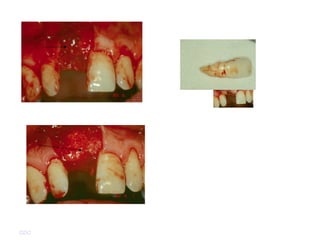

 4~7 timesabove a concentration of platelets than peripheral blood plates level  Bone mineral density 1.6~2,2 times increased  Rapid bone formation & earlier maturation. GDC

• 23.

• 24.

 Split thicknessskin graft 후 donor site 의 healing 양상을 비교함 GDC